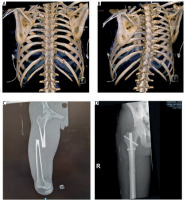

The initial computed tomography (CT) scan revealed: a severe pneumomediastinum; a large right-sided pneumothorax with partial collapse of the lung, small pneumothorax on the left in the apical and anterosuperior region; multiple rib fractures bilaterally, specifically ribs I, II, III, and IV on the left and ribs II, III, IV, VI, VII, and XII on the right (Figures 1A and 1B); fracture of the upper third of the right scapula and right sternoclavicular subluxation; a hepatic subcapsular hematoma at segment VI (approximately 13 × 6 mm); evidence of suspected right renal hematoma; a compound fracture of the left transverse process (Th1); and a fracture of the middle third of the right femoral diaphysis (Figure 1C).

FIGURE 1

A, B) 3D chestcomputed tomography reconstruction with 2 perspectives showing posterior rib fractures. C, D) X-ray of femur fracture on admission to the emergency room and after surgical reduction (one week later)